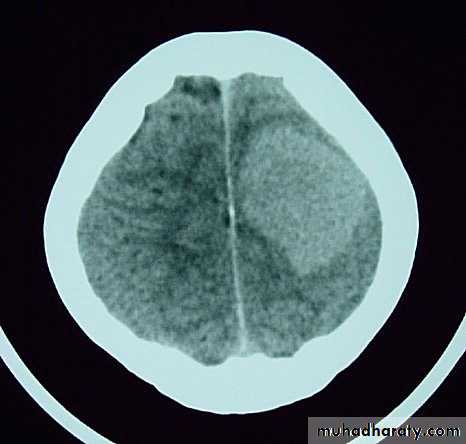

• On CT, they only show well with intravenous contrast.

• Steroids may help reduce peritumour oedema.

• Surgery may be appropriate for an isolated metastasis.

CSF shunt used for lesions causing Hydrocephalus.

• Radiotherapy can be used for multiple metastases.